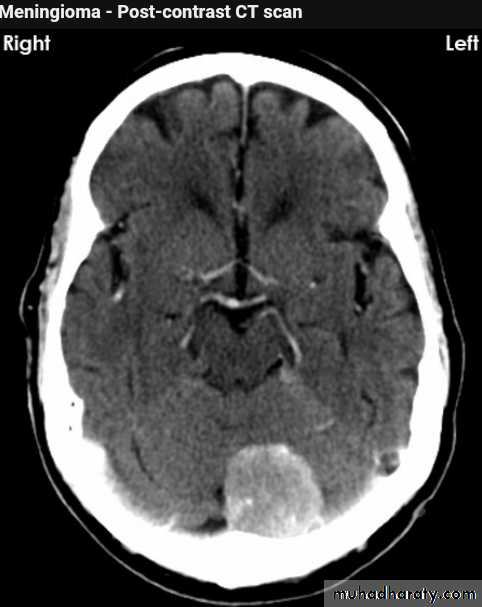

CT finding

meningioma presented as isodense area or slightly hyper density area with surrounded crescent of hypo density ( csf cap ) post contrast injection the lesion enhance homogeneously with enhancing Dural tail .

20 % show calcification

hyperostosis & thickening of the near by bony part of the skull & diplioc space .

it may be associated with little or no peri focal edema .